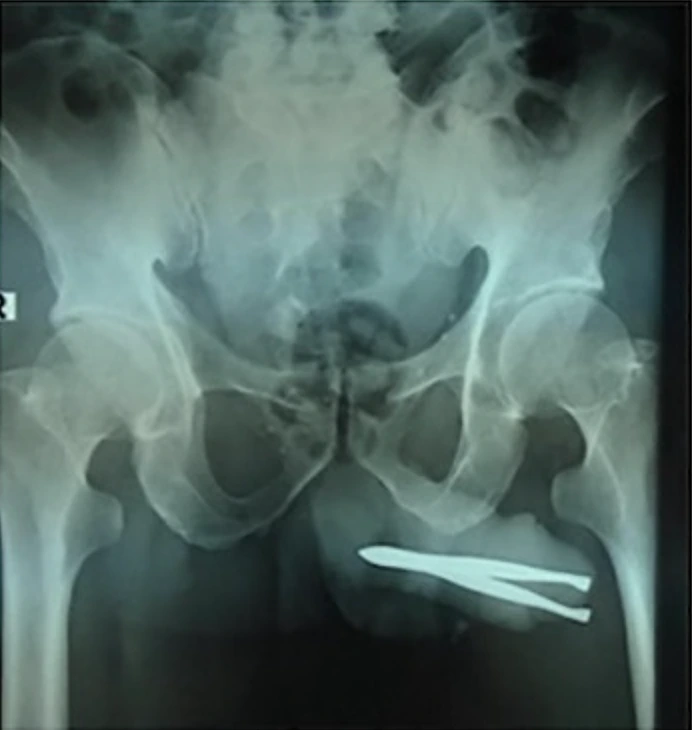

כאשר הרופאים גילו את העצם הזר שחדר לתוך קצה איבר מינו, הם הופתעו לגלות שהוא עדיין היה מסוגל להטיל שתן, אם כי בכאב ובקושי רב. צילומי הרנטגן חשפו את מלוא היקרף הבעיה, שכן הפינצטה הייתה תקועה בחוזקה בדרכי השתן שלו.

הרופאים נאלצו לבצע הליך חילוץ עדין בהרדמה. הם חתכו חתך קטן על איבר המין על מנת להרחיב את פתח השופכה ולהסיר את הפינצטה בבטחה. לאחר מכן הם סגרו את הפצע עם שלושה תפרים. למרבה המזל לא היו סיבוכים כמו דיום או זיהום.